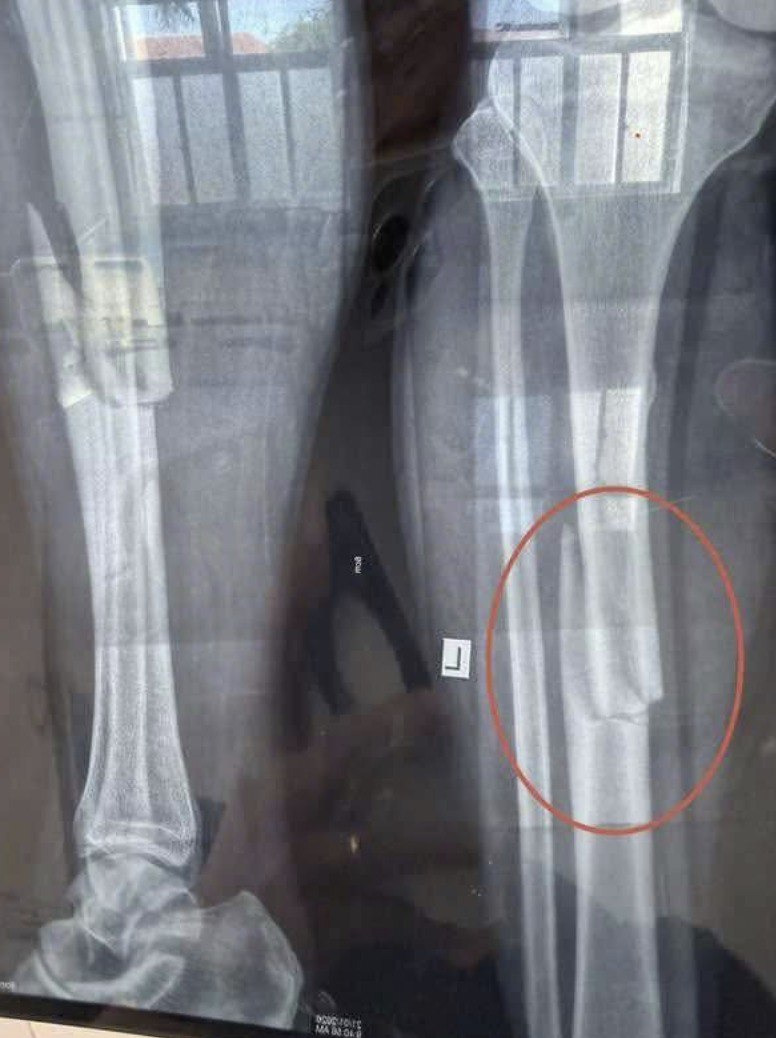

VI:D;E;O 0C;HE: C;ân nh;ắc khi xem Phước Đông – Tây Ninh: TNLĐ trong lúc làm việc khiến nam thanh niên gãy chân. làm việc chú ý nha mọi người http://cafe60giay.com/wp-content/uploads/2026/01/M5b8lwBE1.mp4 http://cafe60giay.com/wp-content/uploads/2026/01/whIxeOqb1.mp4